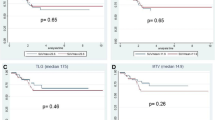

Results from univariate linear regression analysis comparing metabolic parameters to TRG groups are shown in Fig. 1. Among all the metabolic parameters considered in our study, a direct significant correlation with TRG groups was found for SUV2 (P = 0.048) and mostly for SUV3 (P = 0.009), but only the latter parameter was significantly correlated to TRG in a multivariate analysis (P = 0.002).

In order to find out the most accurate metabolic variable predicting pathologic response to treatment, ROC curves were calculated (Table 3, Fig. 2). The highest accuracy in predicting the response to treatment was obtained with a SUV3 cut-off value of 4.4. With this threshold, FDG uptake at PET/CT3 was true positive (TP) for TRG response in 17 patients, true negative (TN) in eight patients, false positive (FP) in one patient, and false negative (FN) in five patients, resulting in a sensitivity, specificity, accuracy, positive predictive value (PPV), and negative predictive value (NPV) of 77.3%, 88.9%, 80.7%, 94.4%, and 61.5%, respectively. As shown in Table 3, a similar value of accuracy (78.6%), but with a lower PPV (88.2%) was obtained with a SUV2 and a threshold value of 7.3. In Figs. 3 and 4 an example of metabolic responder and non responder patient is shown respectively.

In our study, ROC curves analysis (Fig. 2, Table 3) have shown that SUV3 has the best accuracy (80.7%) in predicting response to neoadjuvant treatment with a threshold value of 4.4. Similar accuracy (78.6%) was obtained for SUV2 with a threshold of 7.3, but with a lower specificity and PPV. It is of interest to note that in our study the PPV of SUV3 in predicting response was very high (94.4%) suggesting more conservative surgical approaches only in patients with evidence of lower glucose uptake at the end of neoadjuvant treatment. On the other hand, NPV was quite low (61.5%), due to the presence of high SUV values, ranging from 5.5 to 6.9, in five patients with TRG 2 (FN). At histology, even if not homogeneously, an inflammatory component was found in almost all patients and this could explain the persistent metabolic activity after the radiation therapy, as previously addressed by other authors [29, 30].